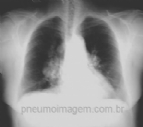

NOVA FASE DO ESTUDO PLATINO DEMONSTROU SUBDIAGNÓSTICO DA DPOC EM SÃO PAULO

A DPOC é uma doença subdiagnosticada e subtratada, o que gera maior morbidade, mortalidade e um grave impacto econômico no sistema de saúde. Há dez anos, o Projeto Latino-Americano de Investigação em Obstrução Pulmonar (PLATINO) observou qu...